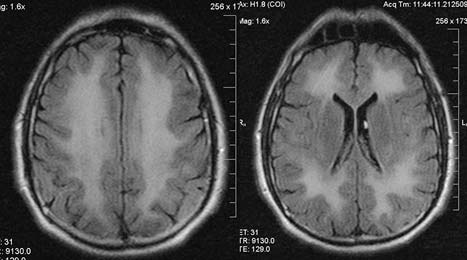

Осмотр через полгода. Общее состояние удовлетворительное. Сознание ясное. Во времени и пространстве ориентирован. Команды врача выполняет сразу, правильно. Эмоционально неустойчив, раздражителен. MoCa-тест — 25 баллов. Пациент себя обслуживает, ведёт активный образ жизни: катается на лыжах, социализирован, в быту независим. Со стороны неврологического статуса обнаружена легко выраженная неврологическая симптоматика в форме повышения глубоких рефлексов, выше слева.

Результат МРТ пациента представлен на рис. 3.

Рис. 3. Магнитно-резонансная томограмма пациента через полгода после эпизода отравления угарным газом

Таким образом, пациент поступает с острым отравлением угарным газом, которое оценили в отделении токсикологии как отравление тяжёлой степени. После проведения дезинтоксикационной, симптоматической, антидотной, антибактериальной терапии в удовлетворительном состоянии выписан домой. Дома в течение 3 дней чувствовал себя настолько хорошо, что пытался водить автомобиль. Затем появляется и нарастает психическая и неврологическая симптоматика, которая выражается в неадекватности поведения, возбуждении пациента, утрате контроля функций тазовых органов и способности обслуживать себя, нарушении ходьбы и пр. Ухудшение состояния больного приблизительно охватывает 3 нед. При МРТ обнаружены сливные симметрично расположенные очаги демиелинизации в левом и правом полушариях головного мозга, распространяющиеся от лобной до затылочной доли.

Отмечены положительный эффект от приёма глюкокортикоидов и почти полный регресс психоневрологического дефицита к концу года наблюдения.

«Светлый промежуток» с отсроченностью клинических проявлений обусловлен, с одной стороны, определёнными сроками, которые необходимы для формирования иммунного ответа (поздний иммунный ответ формируется через 96 ч и более), с другой стороны — постепенно нарастающим в результате иммунного повреждения поражением нервной ткани. Данное предположение подтверждается результатами нейровизуализации в динамике — у больного по данным МРТ, сделанной на 2-й день после первых симптомов ОПЛ, уже определялись очаги демиелинизации (см. рис. 1), площадь их вместе с нарастанием клинических симптомов увеличивалась (см. рис. 2, 3).